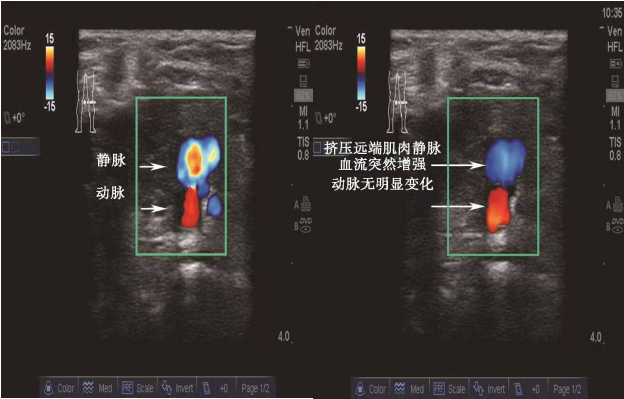

②彩色血流法

找到目标血管后,打开超声的彩色多普勒血流显像时,迎向探头的血流会显示为红色,背离探头的血流显示为蓝色,因此可以结合血管的解剖学基础及超声探头的朝向就可以区分出动静脉。如图A和B均为右侧腘窝处的声像图:图A中探头朝向肢体末端,因此迎向探头的血流(红色)为流回心脏的静脉,而远离探头的血流(蓝色)为流向肢体远端的动脉;图B中的探头方向恰好与A相反,因此红色为动脉,蓝色为静脉。